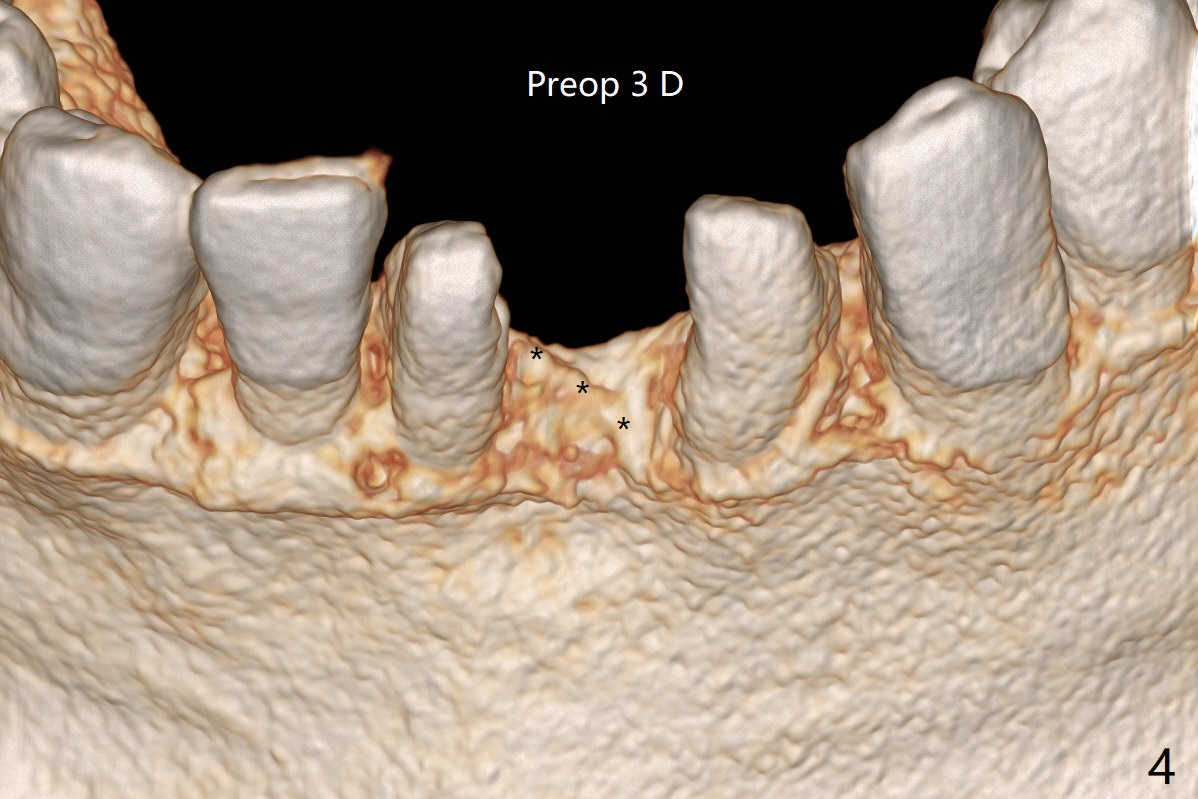

经过深洗以及改善口腔卫生,术前下前牙区牙龈基本没有红肿,但是缺牙处牙龈凹陷(图一,二:箭头),这个现象代表什么?如何影响手术进路?其实后者部分是因为牙龈与下面骨质(骨嵴)粘连(图三:*)产生的,分离粘骨膜瓣时不小心撕裂颊侧牙龈(图三(骨膜分离器下面:#),造成后来缝合困难,需要多用一个胎盘膜)。如果术前仔细分析CT 3D图像(图四,五)可以发现严重颊侧骨壁凹陷(图三:^)以及骨嵴(图四:*),事先抽血制备PRF膜和粘性骨粉,植骨效果好些(图六)。术中发现缺损,再抽血会拖延手术。最后将就用血调袢骨粉,使用胶原膜和胎盘膜覆盖(图七,八)。颊侧裂口术后十天愈合了(图九,十)。术后一个月颊侧牙龈凹陷,牙桥边缘(图十一:箭头)粗糙,临时牙桥取出,调整边缘,有利于局部卫生(图十二)。术后两个月桥边缘光滑(图十三:箭头),局部卫生和牙龈凹陷有所改善。病人将一个半月后回来取模。Return to Protect Graft 前磨牙即种 101 Xin Wei, DDS, PhD, MS 1st edition 04/30/2021, last revision 07/03/2021